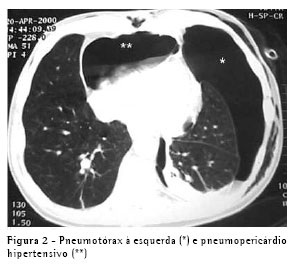

Um paciente do sexo masculino, com 64 anos, apresentando doença pulmonar obstrutiva crônica foi submetido a enxerto bypass de artéria coronária (EBAC) com anastomose de artéria mamária interna direita. Na unidade de terapia intensiva, duas horas após a extubação, ele apresentou pneumotórax espontâneo à esquerda, o qual foi controlado através da inserção de um cateter pigtail 14 Fr, após o quê o paciente melhorou. Porém, dois dias depois, ele apresentou desconforto respiratório e um segundo pneumotórax foi visto apesar do fato de que o cateter pigtail havia permanecido na cavidade pleural e encontrava-se desobstruído. Um segundo cateter pigtail foi inserido em posição anterior.

O problema foi resolvido, e os cateteres foram removidos. No dia seguinte, o paciente apresentou hipotensão, taquicardia e dispnéia. Por motives técnicos, não foi possível realizar um ecocardiograma. A TC mostrou um pneumotórax anterior esquerdo e um pneumopericárdio grande (Figura 2). Um tubo torácico 32 Fr foi inserido na cavidade pleural esquerda, e o problema foi totalmente resolvido. O paciente também foi submetido a uma pleurodese com talco em suspensão. A mesma solução simples (drenagem pleural) foi usada neste segundo caso.